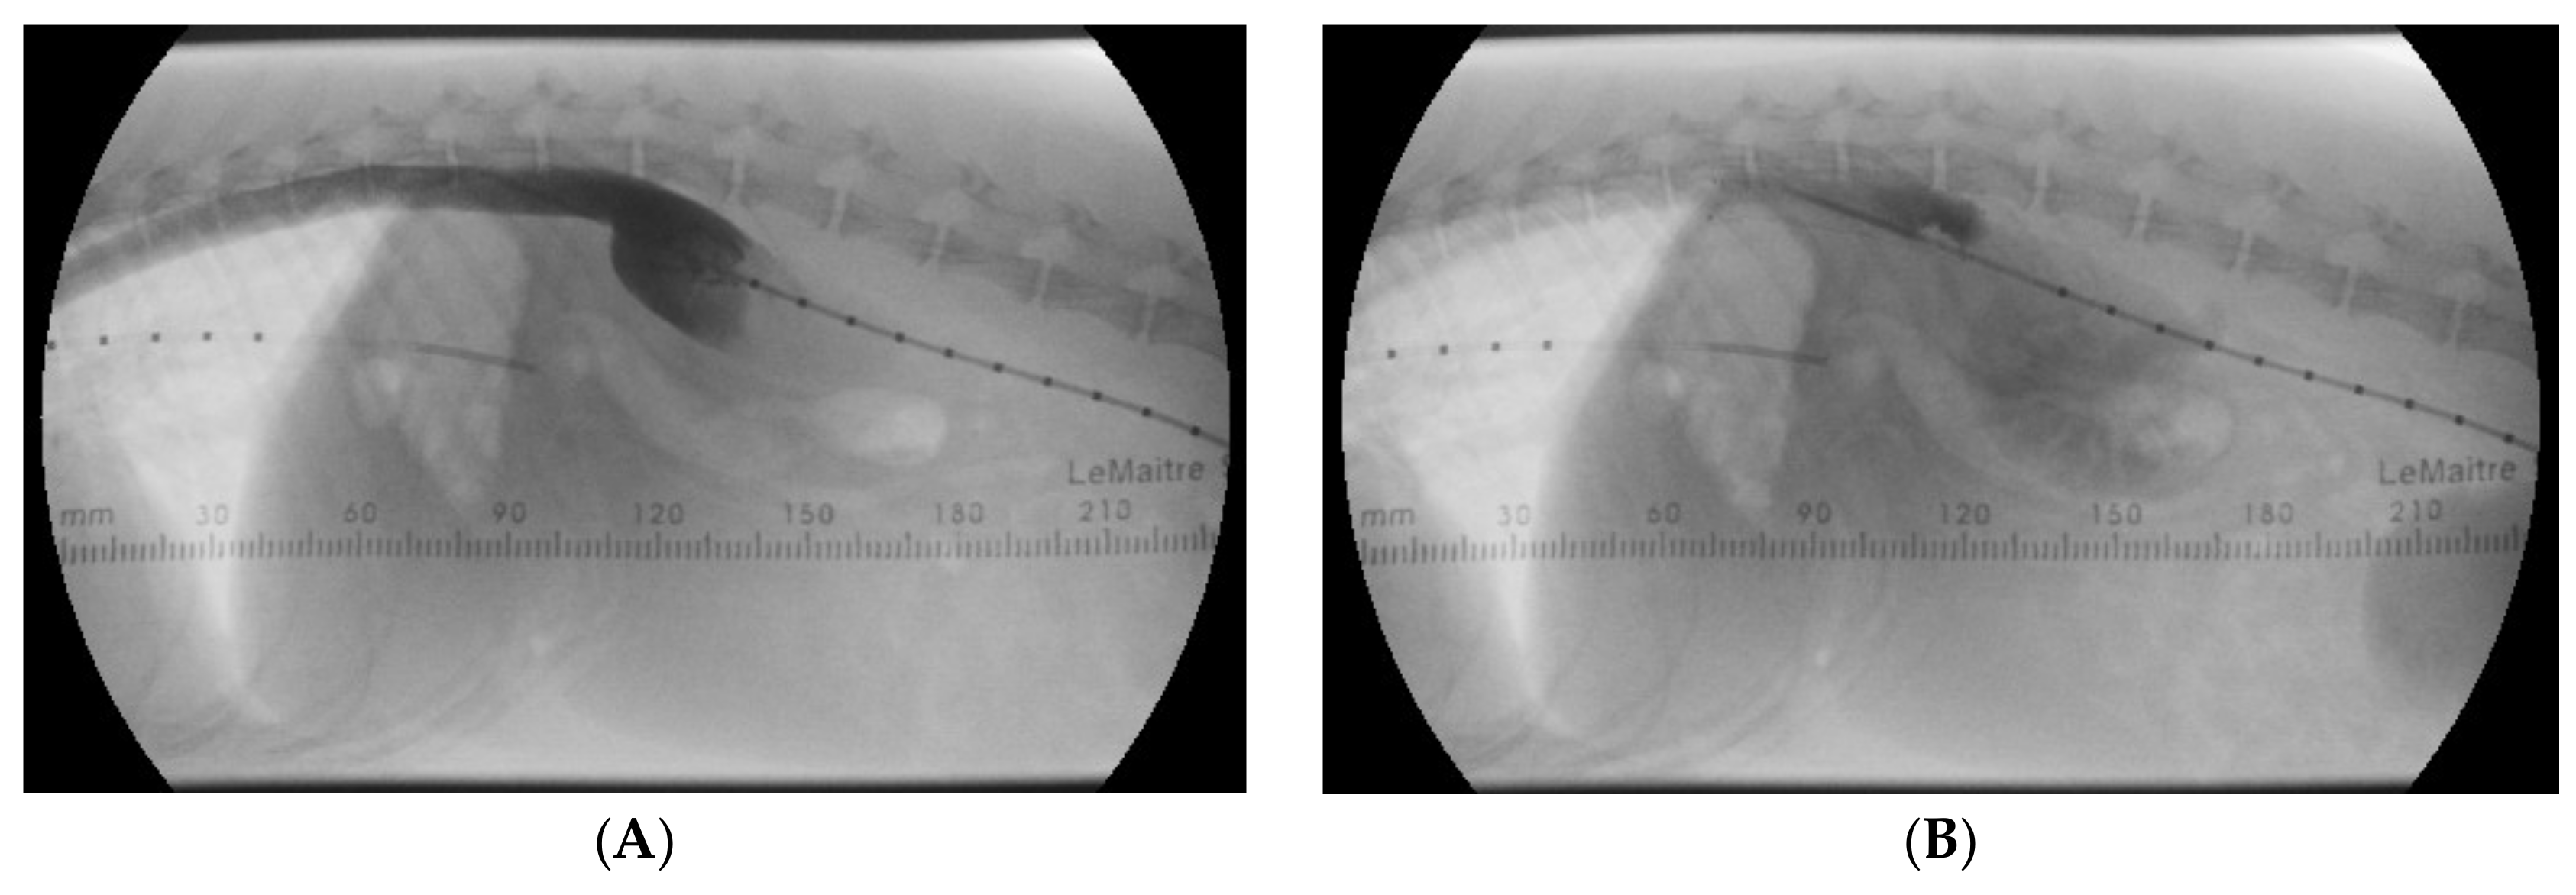

Next, an abdominal ultrasound examination was performed to investigate the abdominal aorta and the CVC. The abdominal aorta showed normal pulsed-wave Doppler flow pattern, but unexpectedly, it was located to the right of the CVC (Figure 2).

Animals 15 00722 g001

Figure 2. Duplex Doppler images of the abdominal aorta (A) and the caudal vena cava (B) caudal to the kidneys show normal spectral flow pattern in both vessels using pulsed-wave Doppler technique, but an abnormal anatomical localization, as the caudal vena cava (blue) is located to the left of the aorta (red). These images were obtained from the left lateral abdomen with the dog in right lateral recumbency. On both images left is cranial, right is caudal, top is left and bottom is right. With a normal aortic flow pattern, aortic coarctation was excluded.